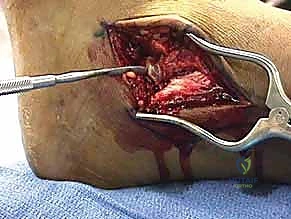

المرحلة الثانية: النهج الجراحي (الشقوق الجراحية)

نظراً لتعقيد عظم الكاحل، غالباً ما يتطلب الأمر شقين جراحيين (Dual Approaches) للوصول إلى العظم من زوايا مختلفة دون تدمير الأنسجة السليمة:

* النهج الأمامي الإنسي (Anteromedial Approach): شق يتم إجراؤه على الجانب الداخلي للكاحل، بين وتر العضلة الظنبوبية الأمامية والكعب الإنسي. يتيح هذا الشق رؤية ممتازة لعنق الكاحل والجانب الداخلي لجسم العظم. في بعض الحالات المعقدة، قد يضطر الدكتور هطيف لإجراء "قطع عظمي للكعب الإنسي" (Medial Malleolar Osteotomy) للوصول إلى عمق المفصل، ثم إعادة تثبيته لاحقاً.

* النهج الأمامي الجانبي (Anterolateral Approach): شق يتم إجراؤه على الجانب الخارجي، يتيح رؤية النتوء الجانبي، المفصل تحت الكاحلي، والجانب الخارجي للعنق والجسم.

المرحلة الثالثة: التنظيف والرد (Reduction)

بعد كشف العظم المكسور، يقوم الدكتور هطيف بحذر شديد بتنظيف منطقة الكسر من التجلطات الدموية، والأنسجة المتمزقة، وشظايا العظام الصغيرة التي قد تعيق التئام الكسر.

هنا تبدأ المرحلة الأهم: "الرد". باستخدام أدوات دقيقة، يتم إعادة القطع العظمية المكسورة إلى مكانها التشريحي الأصلي بدقة مليمترية. يتم تثبيت القطع مؤقتاً باستخدام أسلاك كيرشنر (K-wires) الدقيقة.